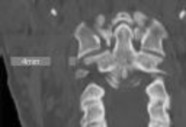

Figures 1 and 2 are CT scans obtained from a 68-year-old man who has had

progressive neck pain and stiffness, worsening gait imbalance, upper extremity weakness, early muscle fatigue, difficulty with fine motor control, and difficulty with activities of daily living over the past few years. On physical examination, he has a wide based stiff legged gait, generalized upper extremity weakness, dense sensory loss in the upper and lower extremities, and markedly brisk reflexes. What is the most appropriate treatment for this patient?

4. Posterior cervical laminoplasties from C3-6 Discussions: D

This patient has progressive myelopathy secondary to ossification of the posterior longitudinal ligament. Diagnostic imaging reveals multilevel cervical cord compression from C4-6. The patient has maintained reasonable cervical lordosis. A posterior procedure such as multilevel laminoplasty

decompresses the spine, is motion preserving, and has a low complication rate. Observation and cervical epidural injections are not viable options in patients with progressive myelopathy. Anterior cervical decompression, including corpectomy, is an option; however, anterior procedures have an increased risk of complications such as dural tear or cerebrospinal fluid leak. The axial CT image shows a "double layer" sign, which is consistent with dural ossification and increases the risk of dural injury with anterior decompression